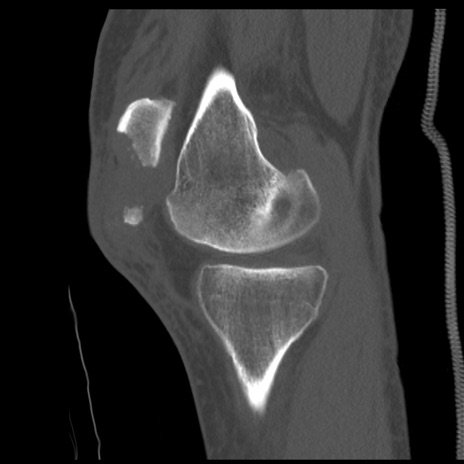

症例28 右膝関節CT(矢状断像)

右膝関節CT

横断像